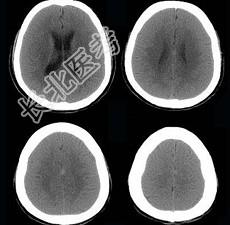

- 单项选择题男,57岁, 头痛、头晕1周,言语不清, 饮水呛咳两天,既往有鼻咽癌病史, 给予放射治疗,CT检查如图所示, 最可能的诊断是 ( )

A、放射性脑病

B、脑梗死

C、脱髓鞘病变

D、胶质瘤

E、脑炎